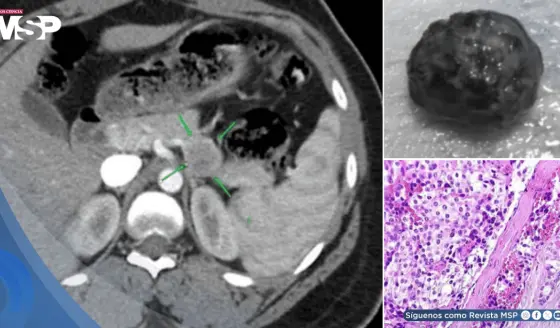

Carcinoma pulmonar oculto tras dolor lumbar y ciática: Pseudoprogresión después de terapia neoadyuvante